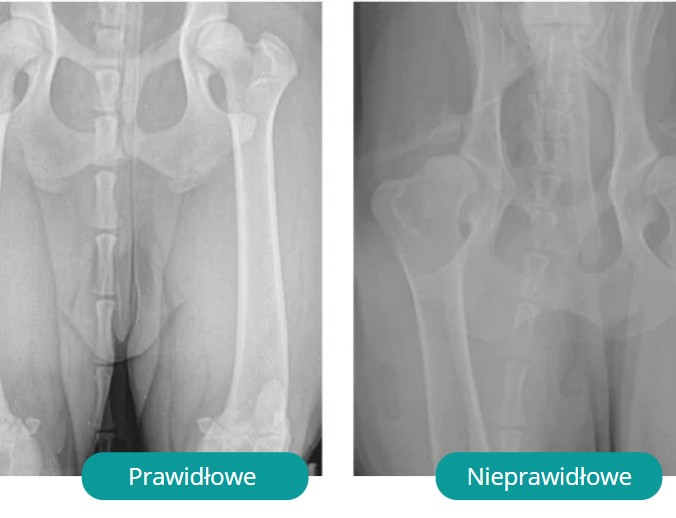

Badania obrazowe

RTG stawów w znieczuleniu – podstawowe badanie do określenia rodzaju dysplazji.

Metody OFA – oceniają strukturę oraz głębokość pokrycia stawu biodrowego.

PennHIP – mierzą dwustopniowo luźność stawu (dyskrekcja + kompresja).

CT (tomografia) – najlepsze w wykrywaniu dysplazji łokciowej.

W Polsce obowiązują badania u wybranych ras – wynik wpisuje się do rodowodu (A–E), decydując o dopuszczeniu do hodowli.